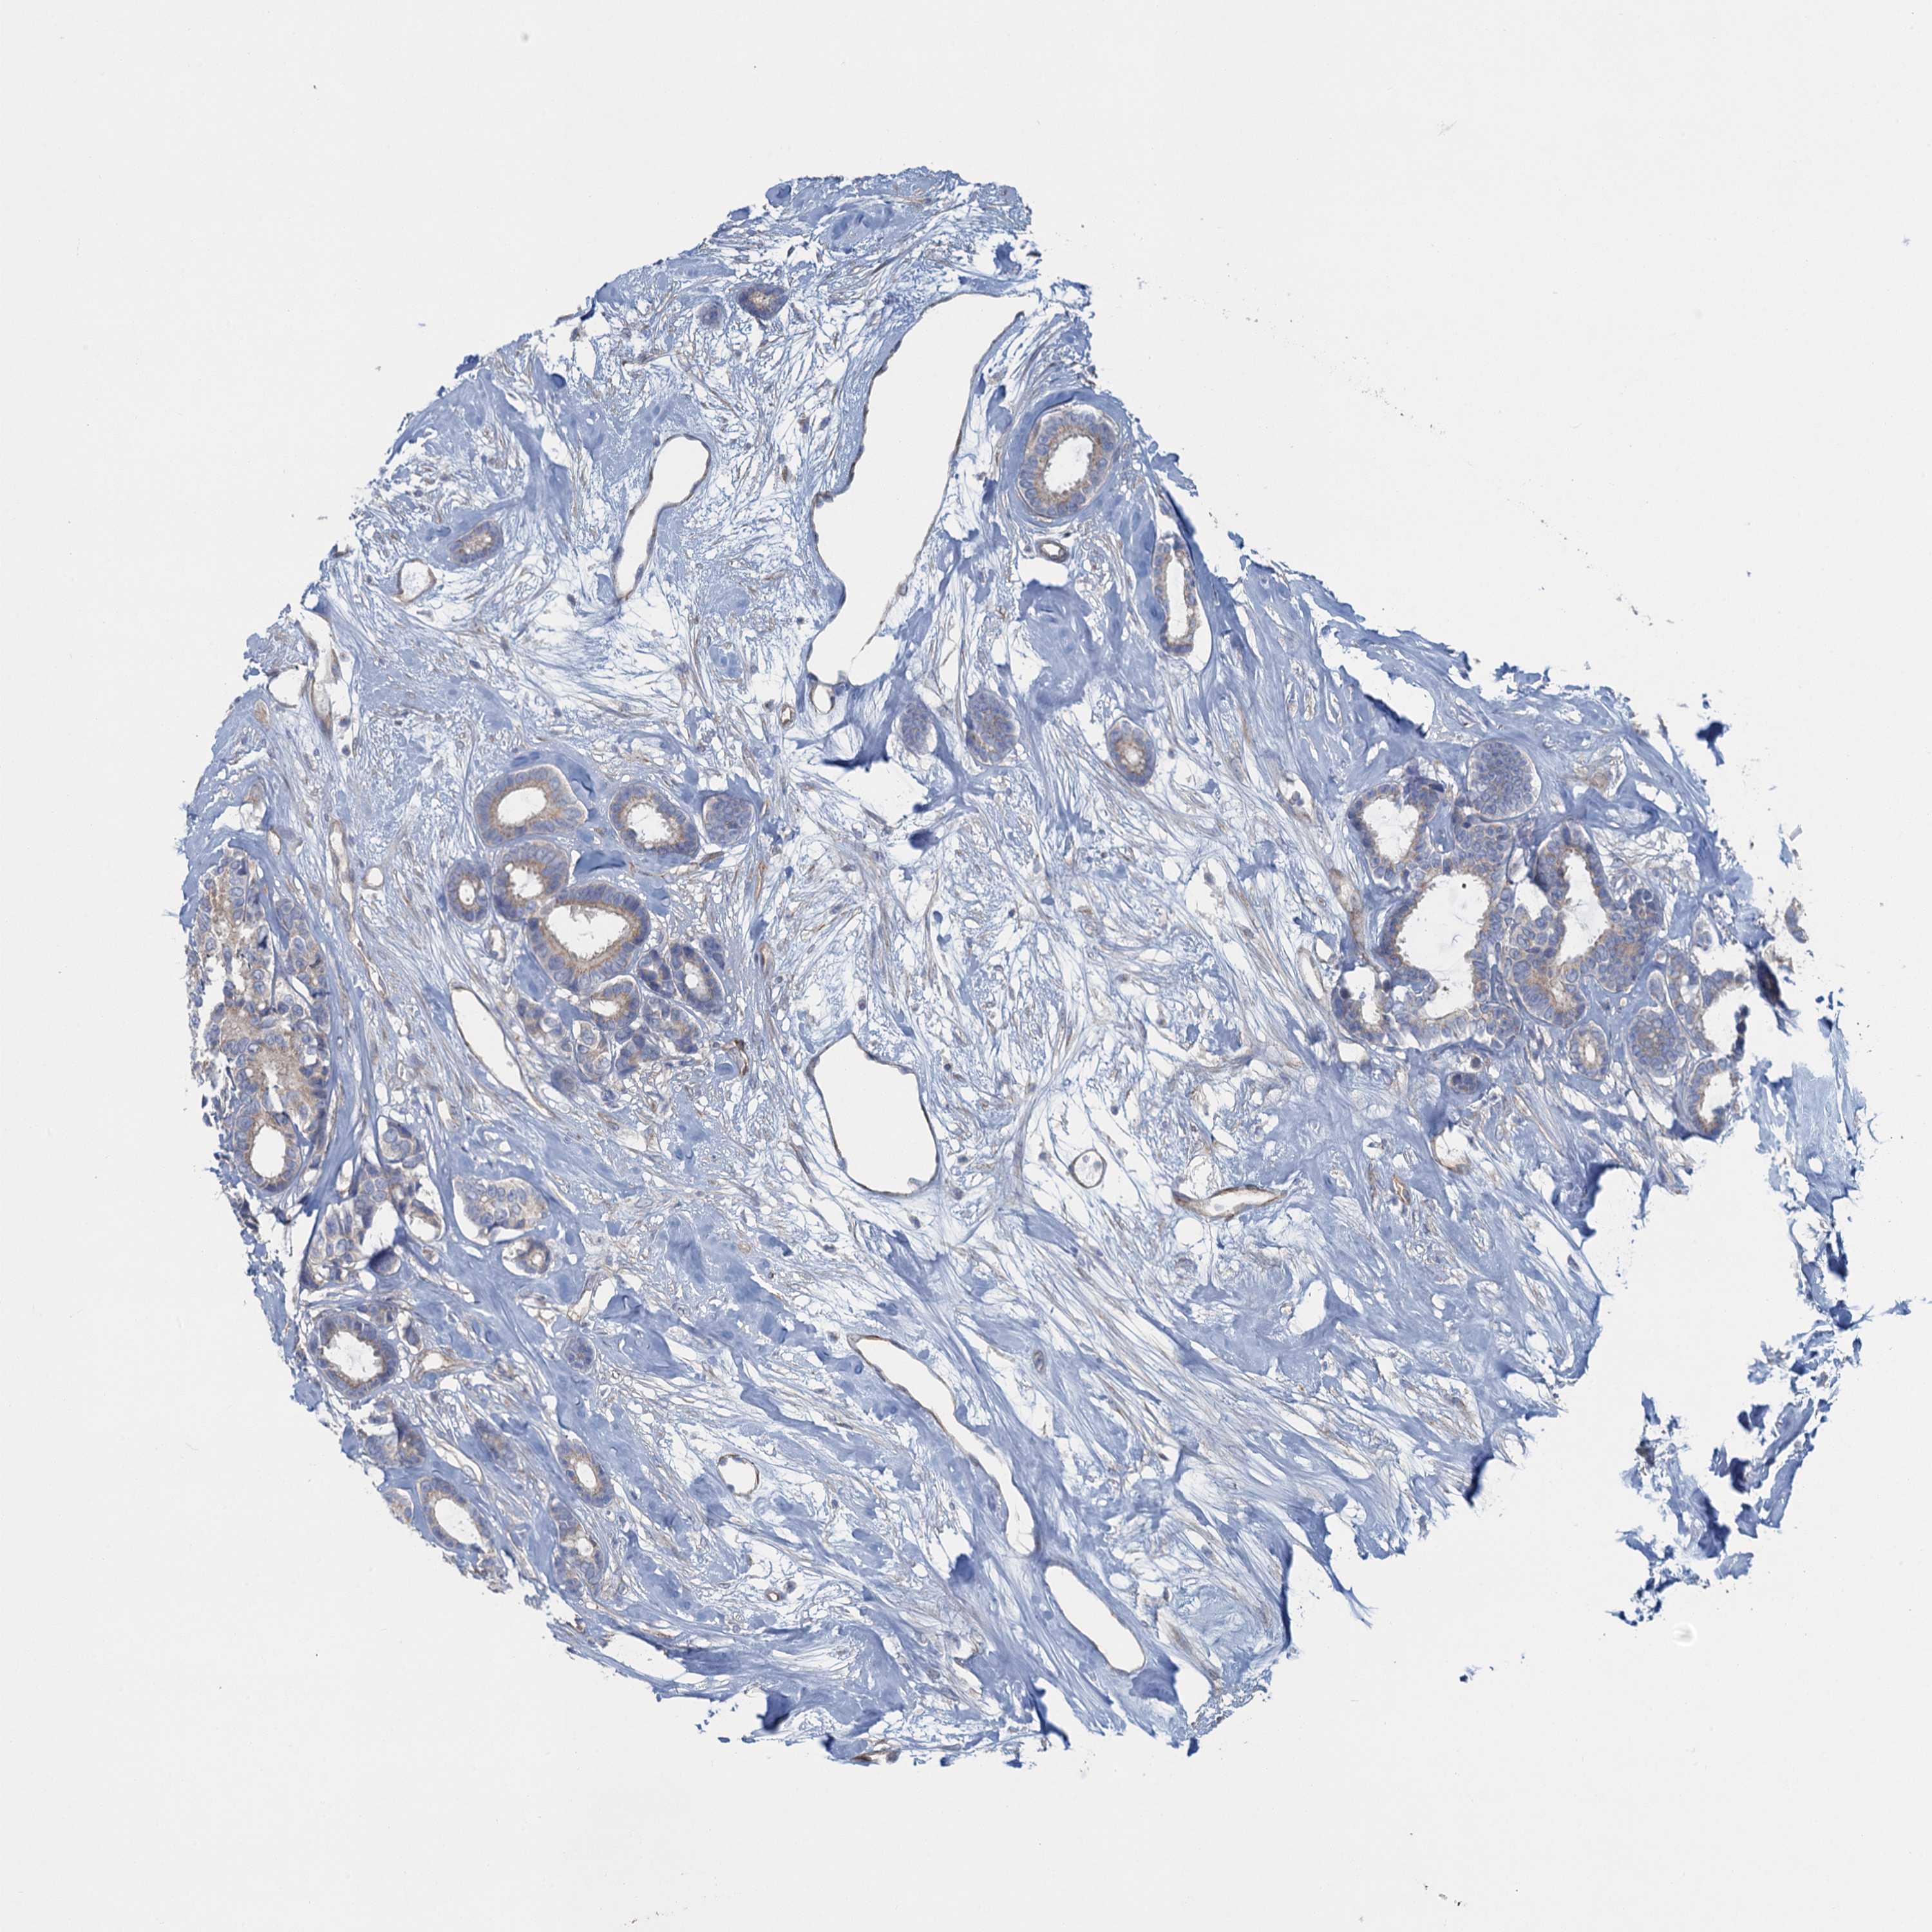

CANCER BREAST CANCER Show tissue menu

BRCA TCGA BRCA VALIDATION PROTEIN EXPRESSION